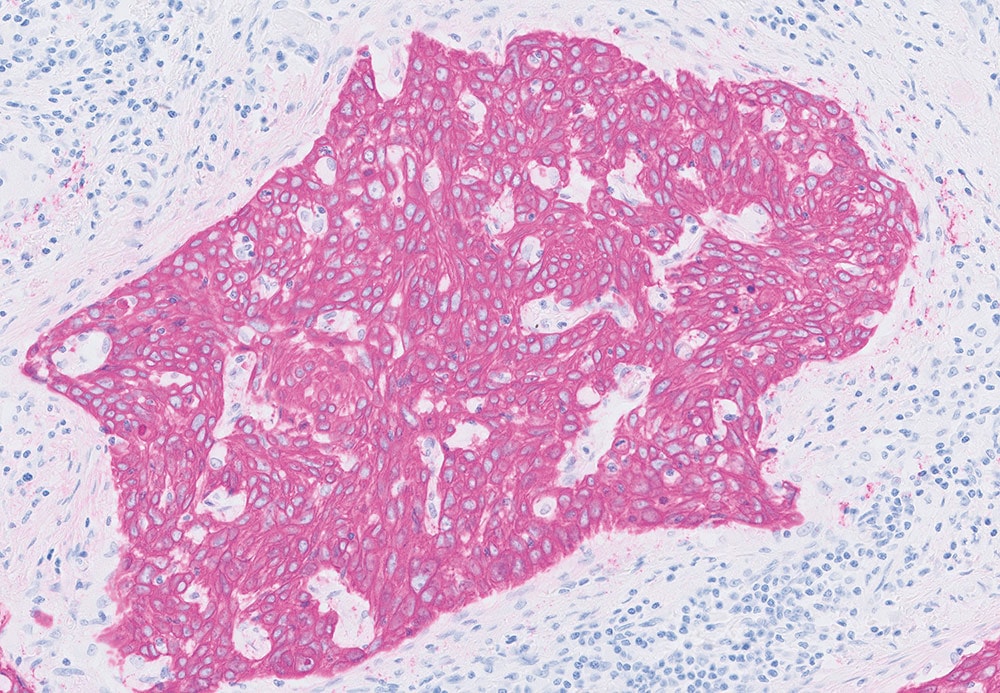

When diagnosing cancer, pathologists typically stain tumor samples with a brown stain called DAB. However, for skin and lung biopsies, they usually choose a red stain as it contrasts well with the brown melanin color in skin, and any pollution artifacts that are typical in lung tissue.

HRP Magenta has a transparent nature, yet is clearly visible, distinct and intense. This allows the pathologist to recognize tissue structures and cellular details even in strongly stained cases. Nuclei can be easily identified, and all details are visible.

HRP Magenta is designed for use on Dako Omnis, the company's flagship instrument for immunohistochemistry and in situ hybridization. Derived from a well-known chromogen used for many years in other industries, the molecule has been modified for use in cancer diagnostics.

HRP Magenta, used with the Dako EnVision FLEX visualization system for Dako Omnis, enables laboratories to stain with two colors—brown and magenta—occupying only few additional vial spaces in the instrument. This added flexibility is expected to enable a leaner workflow with quicker turnaround times for faster patient diagnoses.